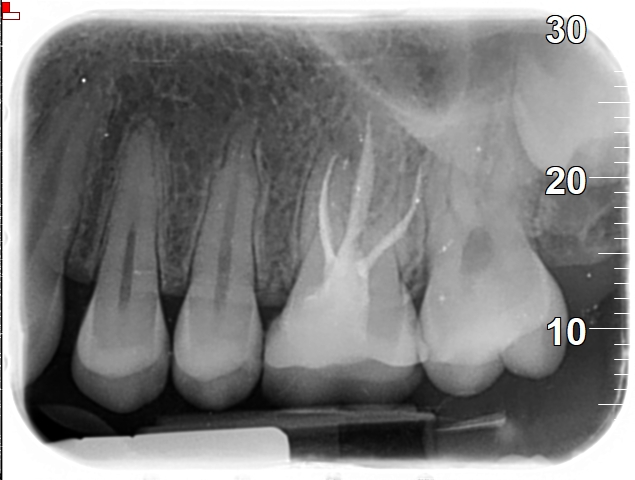

השימוש ב-PRF בטיפולי שורש:

• לאחר ניקוי וחיטוי תעלות השורש, ניתן להחדיר לתוכן PRF בטכניקה מדויקת

• הימצאותו בתוך התעלה מעודד התחדשות של כלי דם ותאי מוך חדשים

• משמש בגישות של רה-וסקולריזציה (Revascularization)= בנייה מחדש של כלי הדם בתוך מוך השן.